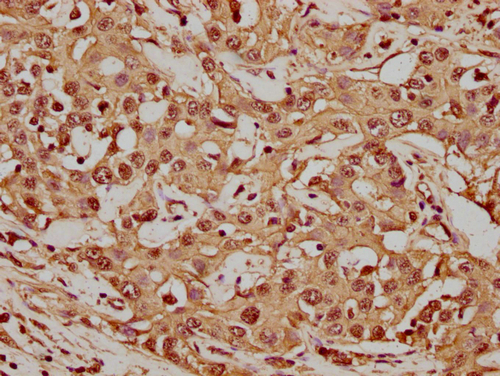

• IHC image of CSB-PA010418PA56nme1HU diluted at 1:20 and staining in paraffin-embedded human colon cancer performed on a Leica BondTM system. After dewaxing and hydration, antigen retrieval was mediated by high pressure in a citrate buffer (pH 6.0). Section was blocked with 10% normal goat serum 30min at RT. Then primary antibody (1% BSA) was incubated at 4°C overnight. The primary is detected by a biotinylated secondary antibody and visualized using an HRP conjugated SP system.

• IHC image of CSB-PA010418PA56nme1HU diluted at 1:20 and staining in paraffin-embedded human liver cancer performed on a Leica BondTM system. After dewaxing and hydration, antigen retrieval was mediated by high pressure in a citrate buffer (pH 6.0). Section was blocked with 10% normal goat serum 30min at RT. Then primary antibody (1% BSA) was incubated at 4°C overnight. The primary is detected by a biotinylated secondary antibody and visualized using an HRP conjugated SP system.